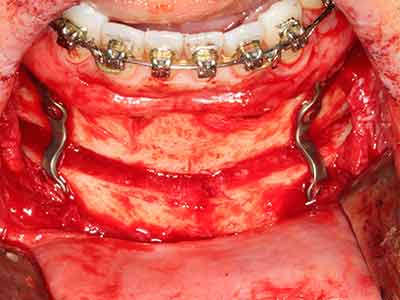

Knochengewebe ist nicht nur rein mineralisch, sondern auch in wesentlichen Anteilen aus Kollagenfasern aufgebaut. Dies gewährleistet neben einer guten Druckfestigkeit eine gewisse Flexibilität, welche für die Durchführung von Augmentationen genutzt werden kann. Bei der klassischen Expansionsplastik im Sinne eines Bone Splittings wird der atrophierte Kieferkamm in seiner Längsachse gespalten und nach Erreichen einer ausreichenden Osteotomietiefe vorsichtig aufgedehnt (Abb. 13-16), idealerweise ohne den Kiefer wesentlich zu deperiostieren (Brugnami, Caiazzo et al. 2014, Stricker, Fleiner et al. 2014). Bewährt haben sich Schrauben- und Plattensysteme mit zunehmender Expansionsdistanz, um die beiden Knochenlamellen unterhalb der Bruchschwelle voneinander zu distanzieren. In der Regel werden Restknochenbreiten von mindestens 3-4 mm gefordert (Chiapasco, Zaniboni et al. 2006), um eine ausreichende Flexibilität und knöcherne Bedeckung der einzubringenden Implantate zu gewährleisten. Ggf. kann eine ein- oder beidseitige vertikale Entlastungsosteotomie die Flexibilität verbessern. Als Alternative zur klassischen Technik wurde eine Kombination mit weiteren augmentativen Techniken vor allem auf der bukkalen Seite beschrieben.

Mittels Piezosägen erfolgt die Anlage des Splittings besonders schonend und ohne wesentliche Dimensionsverluste, so dass sich keine signifikanten Unterschiede von Implantaten im gesplitteten Kiefer im Vergleich zum nicht defizitären Alveolarkamm gezeigt haben (Chiapasco, Zaniboni et al. 2006, Danza, Guidi et al. 2009). Gerade beim lokal begrenzten und tiefen Splitting ist jedoch stets auf eine ausreichende Wasserkühlung zu achten, um thermische Belastungen in den apikalen Osteotomiebereichen zu vermeiden.